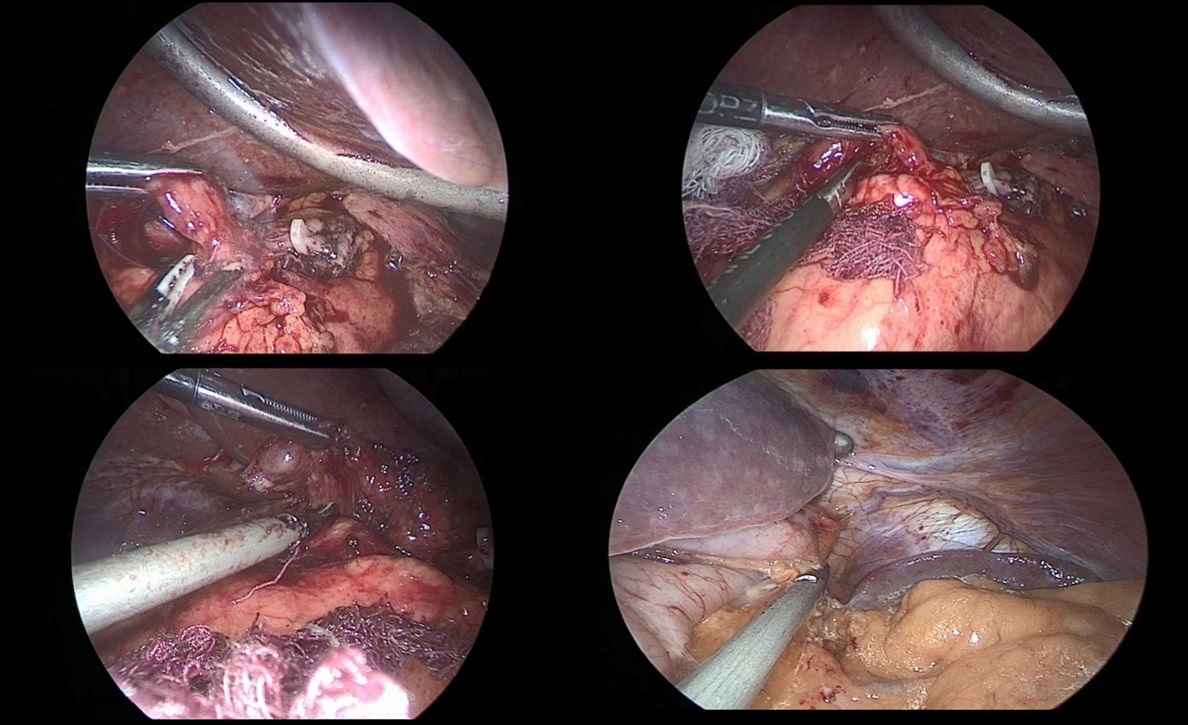

After crossing the pyloric sphincter, laparoscopic lymph node dissection of the VII, VIIIa, IX, XI, XIIa groups of lymph nodes was performed (Figure 9 a, b, c, d).

Figure 9a,b,c,d: Lymph node dissection of the hilum of the liver and celiac trunk.